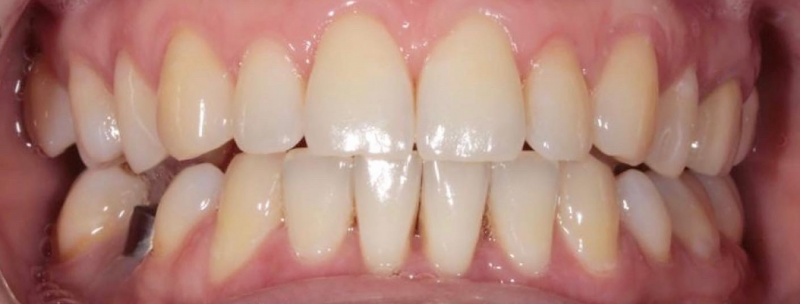

На странице представлено портфолио стоматологий Санкт-Петербурга с работами до и после профессиональной чистки зубов. В нашем портфолио собраны разные клинические случаи: от удаления незначительного налета до снятия массивного поддесневого камня. Здесь вы можете увидеть, как возвращается естественный цвет и внешний вид зубов после процедуры. Изучите результаты до и после чистки зубов, чтобы увидеть реальный эффект и выбрать клинику в Санкт-Петербурге, где профессиональная гигиена поможет вернуть зубам здоровый вид.

Профгигиена